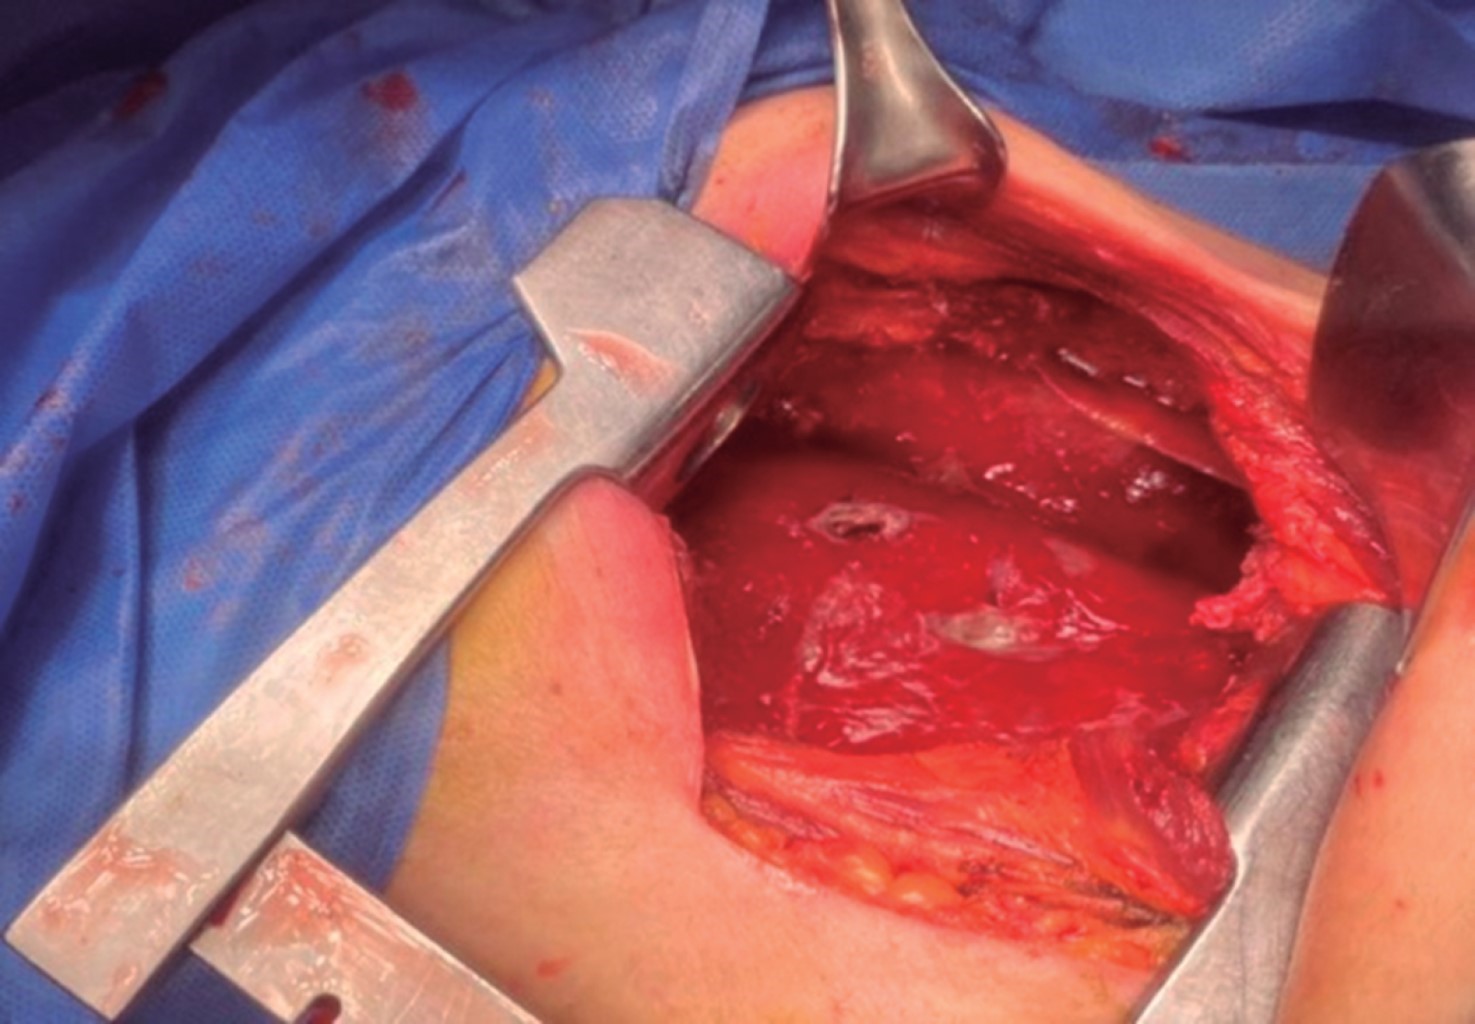

Sin embargo, el paciente evoluciona de manera tórpida, sin lograr reexpansión pulmonar, por lo que se presenta para toracotomía posterolateral derecha el 10-06-20 observando como hallazgos transoperatorios neumonía necrotizante, fístula broncopleural del lóbulo medio derecho y paquipleuritis (Figura 2); se drenaron aproximadamente 200 cm3 de material turbio, se enviaron cultivos y se dejan como drenajes una sonda endopleural y dos drenajes tipo Jackson-Pratt, uno anterior y el otro posterior (Figura 3).

Figura 2